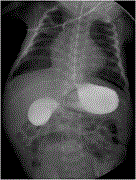

Positive outcome of diaphragm covering and total pleural covering techniques for catamenial pneumothorax

Sachie Koike and others

Journal of Surgical Case Reports, Volume 2023, Issue 7, July 2023, rjad421, https://doi.org/10.1093/jscr/rjad421